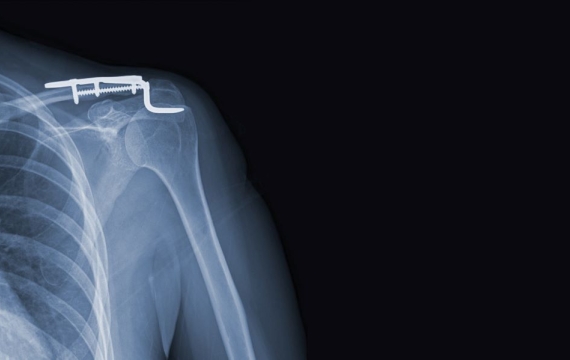

Cirugía de hombro (abierta)

En los casos de colocación de prótesis y para el tratamiento de fracturas que son complejas es necesario realizar la cirugía de hombro abierta. Cuando se realiza la artroplastia de hombro o la implantación de prótesis en la articulación, se realiza a través de una cirugía abierta y la misma consiste en sustituir parte de la articulación o en todo caso la totalidad por una pieza que es artificial.

Tipos de prótesis

Existen 2 tipos de prótesis de hombro:

- Anatómica. Es una prótesis que sustituye la cabeza del húmero

- Invertida. Permite la recuperación de la movilidad en aquellos pacientes con lesiones crónicas en el manguito rotador o con artrosis. Además, en la actualidad se usa esta técnica en fracturas y lesiones en pacientes con edad avanzada.